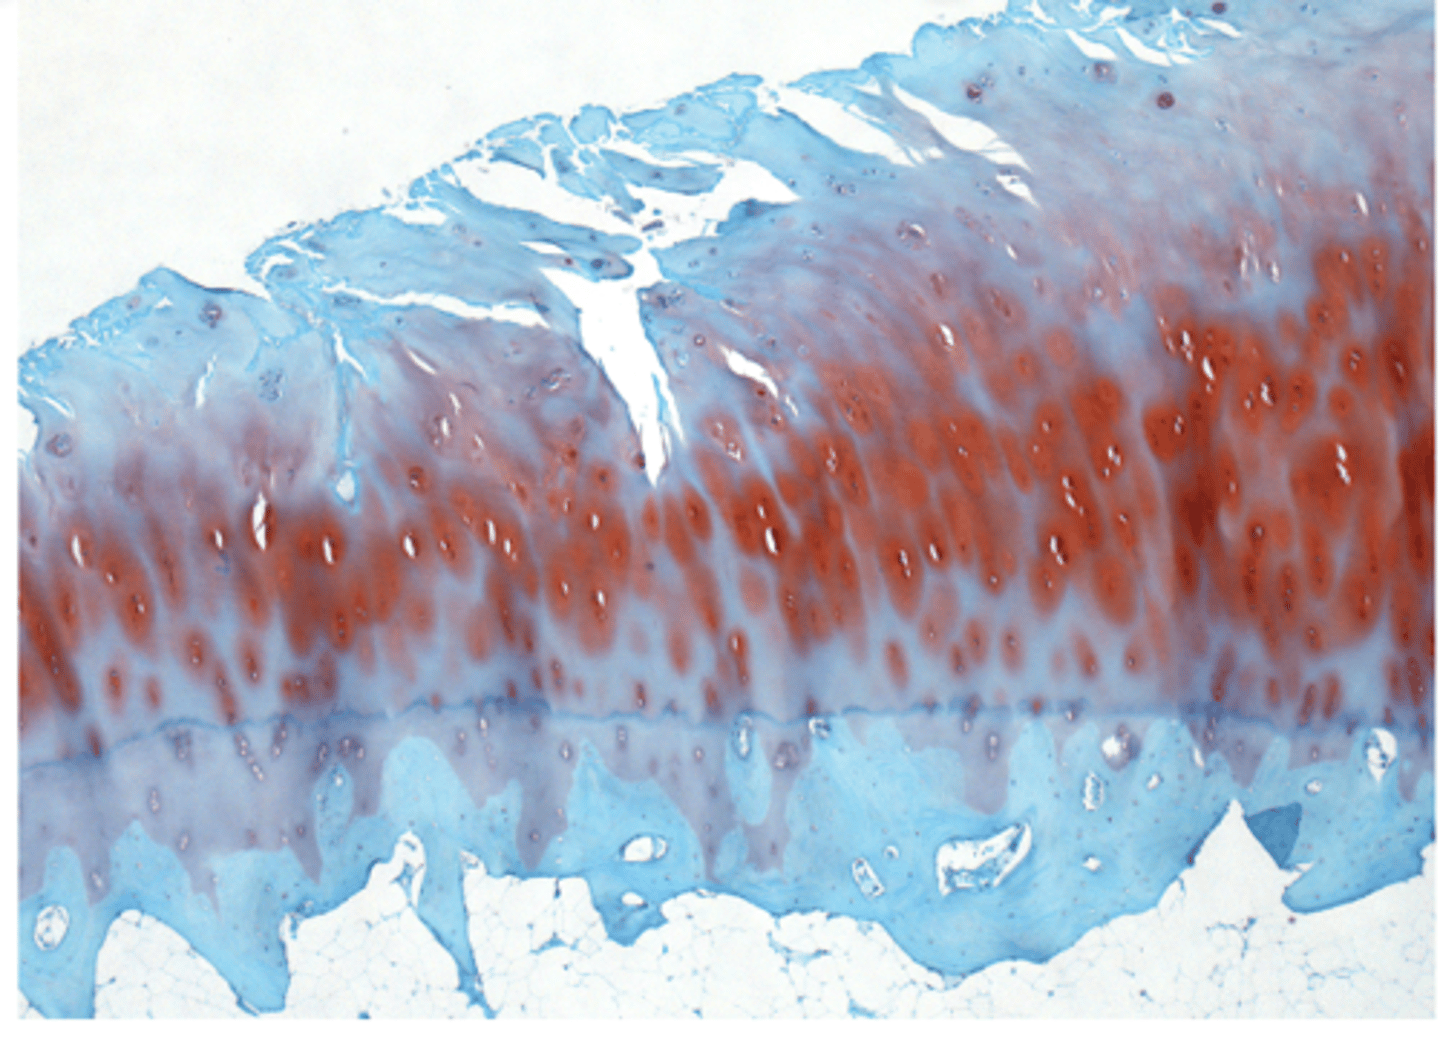

Loss of cartilage in synovial joints

Damaged joint cartilage tries to heal itself

-- Creating osteophytes or spurs

-- Cartilage contains more water, less collagen

-- Cartilage becomes weak, rough, eroded

normal bone/rickets

Osteomalacia

Degradation versus lack of mineralization